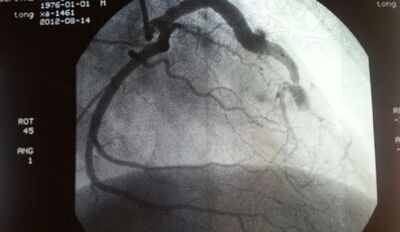

心脏造影是诊断冠心病的金标准,心脏造影检查是将一根很细的导管插入到主动脉,然后通过导管前面的小口向主动脉血液注射造影剂,可以将血管流动的造影剂显示在屏幕中,从而显示出心脏以及血管的形态。

心脏造影有冠状动脉造影和心脏造影。冠脉造影就是用一根细如发丝的导管沿着桡动脉(手腕处)或股动脉(大腿处)的人为入口延行到心脏的冠状动脉开口处,然后把造影剂(在X光下显影)注入冠状动脉。

冠状动脉内部的形态就可以显示出来,但基本上不能通过这个检查来了解心脏形态的,主要还是了解冠脉的内部形态及冠脉内的血流速度。